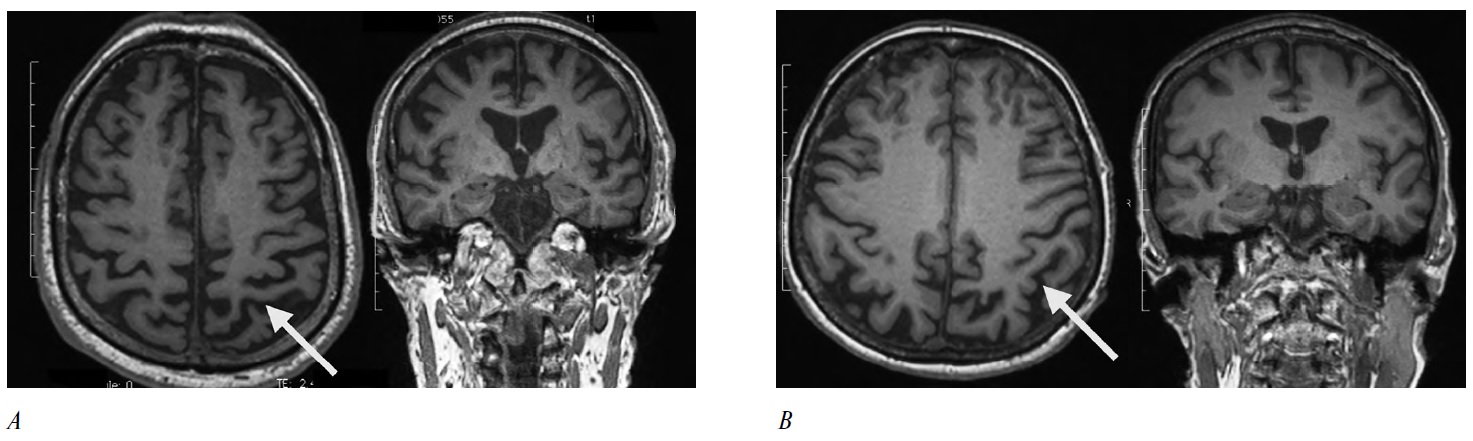

КБС-4R-таупатия. Мужчина, 70 лет. Дебют заболевания в 69 лет, когда появились неловкость в правой ноге и ощущение неустойчивости при ходьбе, пропульсии. Позже присоединилась неловкость в правой руке, нарушился почерк. Приём препаратов леводопы до 750 мг/сут в течение нескольких месяцев — без существенного эффекта. В неврологическом статусе при осмотре через год после дебюта заболевания выявлены глазодвигательные нарушения (нарушения инициации вертикальных саккад, ограничение саккад вверх и снижение их скорости вниз), гипомимия, дизартрофония, выраженное повышение мышечного тонуса в правой руке, брадикинезия при выполнении динамических проб (D > S), постуральные нарушения, застывания при ходьбе, идеомоторная апраксия (D > S). При тестировании по шкалам выявлены умеренные когнитивные нарушения: Адденбрукская шкала — 83/100 баллов, MOCA — 24/30 баллов. При МРТ головного мозга выявлена асимметричная гипотрофия теменной области (рис. 1, А). При люмбальной пункции выявлены нормальные уровни бета-амилоида 1–42 и тау в цереброспинальной жидкости. Нормальные уровни данных маркеров исключают патологию альцгеймеровского типа, а наличие у пациента специфичных глазодвигательных нарушений указывает на нарушение функции рострального интерстициального ядра медиального продольного пучка, что является типичным симптомом ПНП [14]. Таким образом, фенотипы КБС и ПНП часто перекрываются, и в этом случае (как и во многих других аналогичных наблюдениях) клиническая картина не даёт возможности уверенно предположить лежащую в основе синдрома патологию — у данного пациента это может быть как КБД, так и ПНП. Поэтому молекулярный диагноз «4R-таупатии» или «КБС-4R-таупатия» для таких случаев представляется наиболее удобным — особенно с учётом разрабатываемых сегодня таргетных «анти-тау»-препаратов [10].

Рис. 1. МРТ головного мозга пациентов с фенотипом КБС при нормальном соотношении биомаркеров (А) и изменённых биомаркерах (уровень бета-амилоида 1–42 и тау-белка в ЦСЖ — В). Стрелками указаны зоны гипотрофии в теменной области слева (контралатерально клиническим проявлениями) при сохранной области гиппокампа в обоих случаях. / Fig. 1. Brain MRI of patients with the CBS phenotype, the normal ratio (A) and altered biomarkers (β-amyloid 1–42 and tau protein in the CSF — B). Arrows indicate areas of hypotrophy in the left temporal lobe (contralateral to the clinical symptoms), with preserved hippocampus in both cases.

КБС-БА. Женщина, 66 лет. Дебют заболевания в 64 года, когда изменилась чувствительность в правой стопе («как будто приклеили бумагу к стопе»). Через полгода стала отмечать неловкость в правой стопе, появились общая замедленность, неустойчивость, дрожание правой руки и ноги. Через год после дебюта присоединились эпизодические падения. По месту жительства поставлен диагноз болезни Паркинсона. Терапия прамипексолом (3 мг/сут) и амантадином (300 мг/сут) в течение 1,5 лет — без существенного эффекта. При осмотре через 2 года после дебюта выявлена лёгкая мышечная ригидность (D > S), умеренная брадикинезия без декремента амплитуды и скорости (D > S), выраженная идеомоторная апраксия в правой стопе, синкинезии, постуральные нарушения. При оценке когнитивных функций с использованием Адденбрукской шкалы патологии не выявлено (98 баллов), однако при более детальном осмотре нейропсихологом установлены колебания внимания, эмоционально-личностные изменения, снижение слухоречевой памяти в условиях интерференции, изменения в пространственной сфере. Проводилась терапия препаратами леводопы (600 мг/сут) в течение месяца — без эффекта.

При МРТ головного мозга (через 2 года от дебюта) визуализируется гипотрофия левой теменной доли; при этом гипотрофия в области гиппокампов отсутствует (рис. 1, В). При люмбальной пункции выявлен сниженный уровень бета-амилоида 1-42 и повышенный уровень фосфорилированного тау-белка в цереброспинальной жидкости, что, согласно международным исследовательским критериям БА, подтверждает наличие патологии альцгеймеровского типа.

На основании анализа серии случаев предпринимались попытки выделить более характерные для КБС-БА клинические характеристики [5]. Так, например, описано, что в случаях КБС-БА чаще встречаются миоклонии, апраксия одевания, снижение памяти, более низкий балл по шкале MMSE, кортикальный сенсорный дефицит, зрительно-пространственные трудности, неглект-синдром, отсутствие выраженной ригидности в конечностях [5]. При этом наблюдается более длительное течение заболевания по сравнению с КБД [5]. Характерно, что при анализе структурной МРТ наших пациентов с диагнозами КБС-БА и КБС-4R-таупатия (рис. 1) не выявлено специфики — у обоих определяется лишь асимметричная атрофия теменной области (у пациента с КБС-4R-таупатией атрофический процесс более распространённый, с вовлечением лобной области), при этом гиппокампы в обоих случаях сохранны. Это соответствует данным литературы: в случаях КБС-БА обычно описывается латерализованная височно-теменная атрофия, а для КБД характерно вовлечение задних отделов лобных долей [5]. Однако достоверно развести два этих состояния можно только на основании анализов биомаркеров — уровня бета-амилоида 1–42 и фосфорилированного тау-белка в цереброспинальной жидкости, при этом данный анализ не способен выявлять сочетанные формы патологии [5].